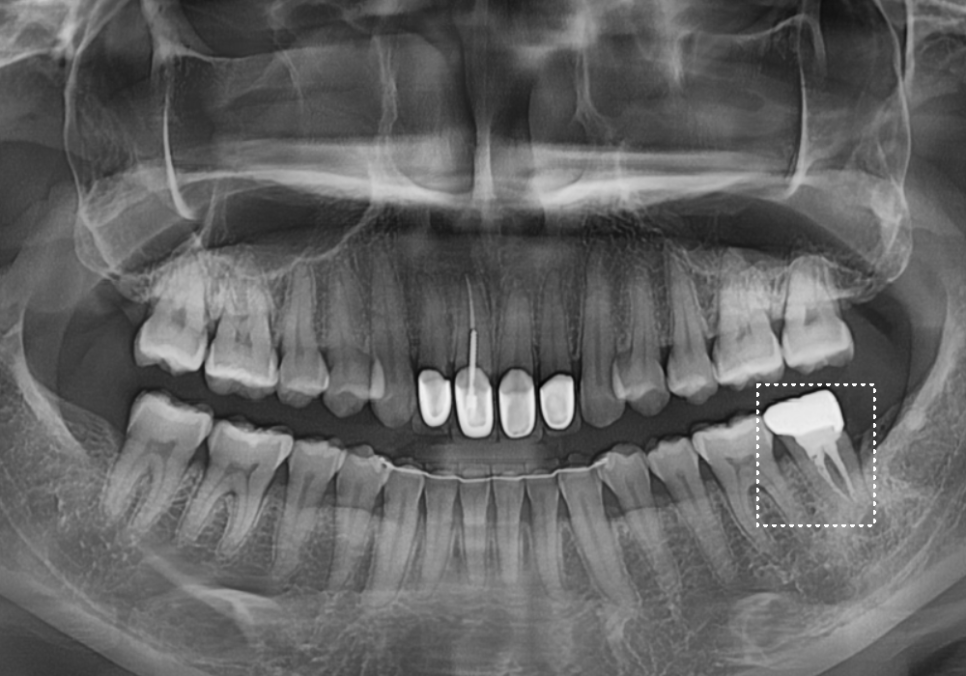

임플란트와 뼈이식, 3개월의 기다림

강동구 치아 뿌리 염증, 신경치료 한 치아인데도 아플 수 있나요?

염증 때문에 녹아버린

잇몸 뼈를 보충하기 위해

임플란트 식립과 동시에

뼈이식을 함께 진행했습니다.

다행히 수술은 아주

안정적으로 잘 마무리되었습니다.

251015

3개월 후, 잇몸 뼈와 임플란트가 하나처럼

단단히 붙은 것을 확인 뒤,

지르코니아로 맞춤 보철물까지

완벽하게 완성해 드렸습니다.^^

2050508(전) 251015(후)